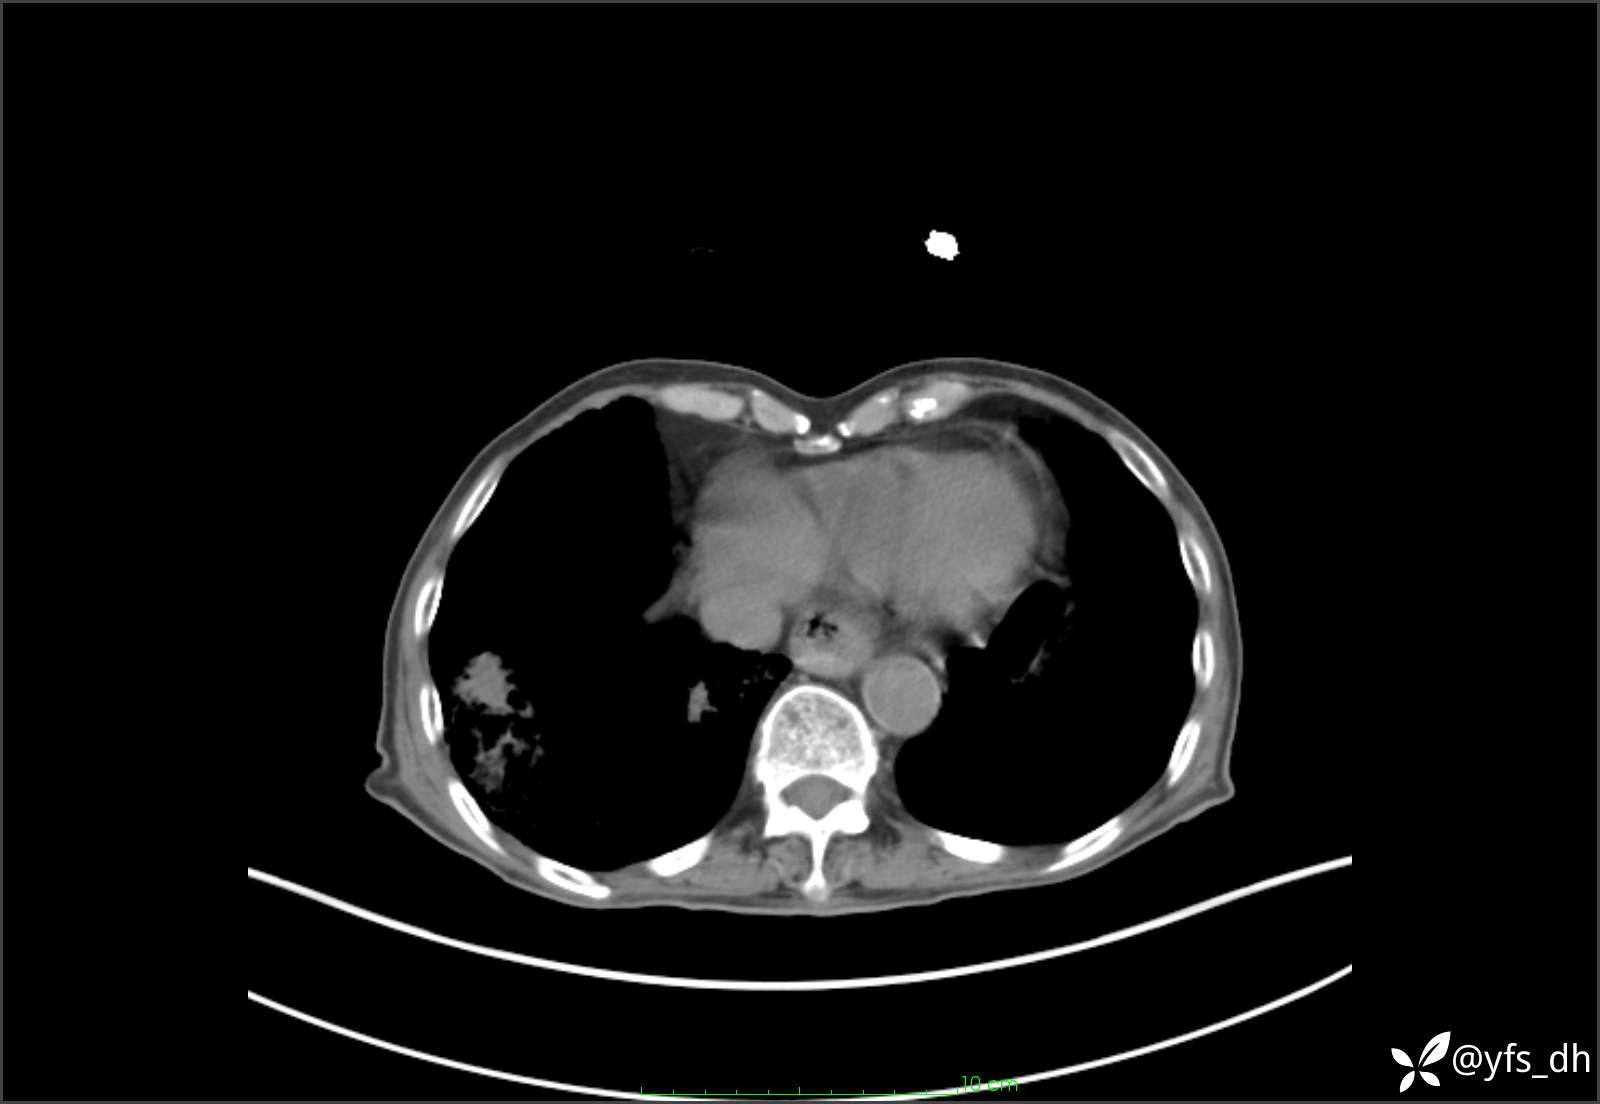

1.简要病史:患者4天前突发上腹部疼痛不适,但可以忍受。3小时前饭后突然加重,不能忍受后就诊。

2.简要手术记录:术中见腹盆腔大量肠液及粪便,乙状结肠中下段见一约3cm的破口。